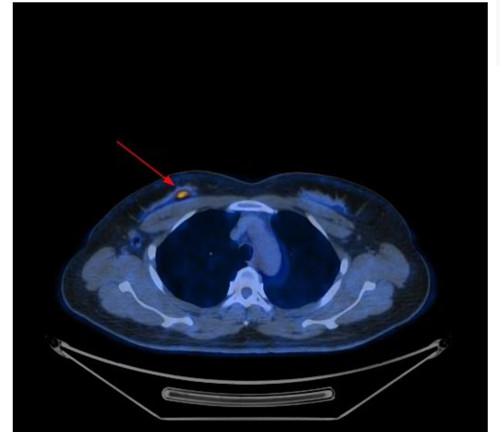

PETCT显示右侧乳腺内糖代谢明显增高的结节和腰椎的转移癌

问题来了,彭女士腰椎转移癌原发灶在哪里?是甲状腺癌吗?因关系后续治疗方案,在医生的建议下,彭女士到捷克论坛 PET影像中心进行PET/CT扫描。检查结果让人大吃一惊,彭女士的右侧乳腺有一个糖代谢明显增高的结节,大小为10mm,高度提示右侧乳腺癌。这下解开了腰椎转移癌的谜底,乳腺癌除腰椎骨转移外,同时发现右侧腋窝淋巴结和骨盆多骨的转移。目前,彭女士已经转入乳甲外科接受手术及进一步治疗。